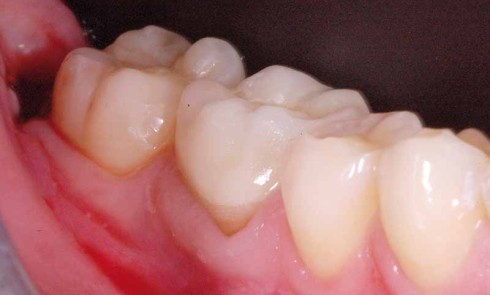

Odontologie restauratrice

Article réservé à nos abonnés Restauration d’une dent dépulpée dans le secteur postérieur

La communication avec le laboratoire C’est une étape connue pour être importante dansla réussite d’une restauration prothétique. Ellea pour but...